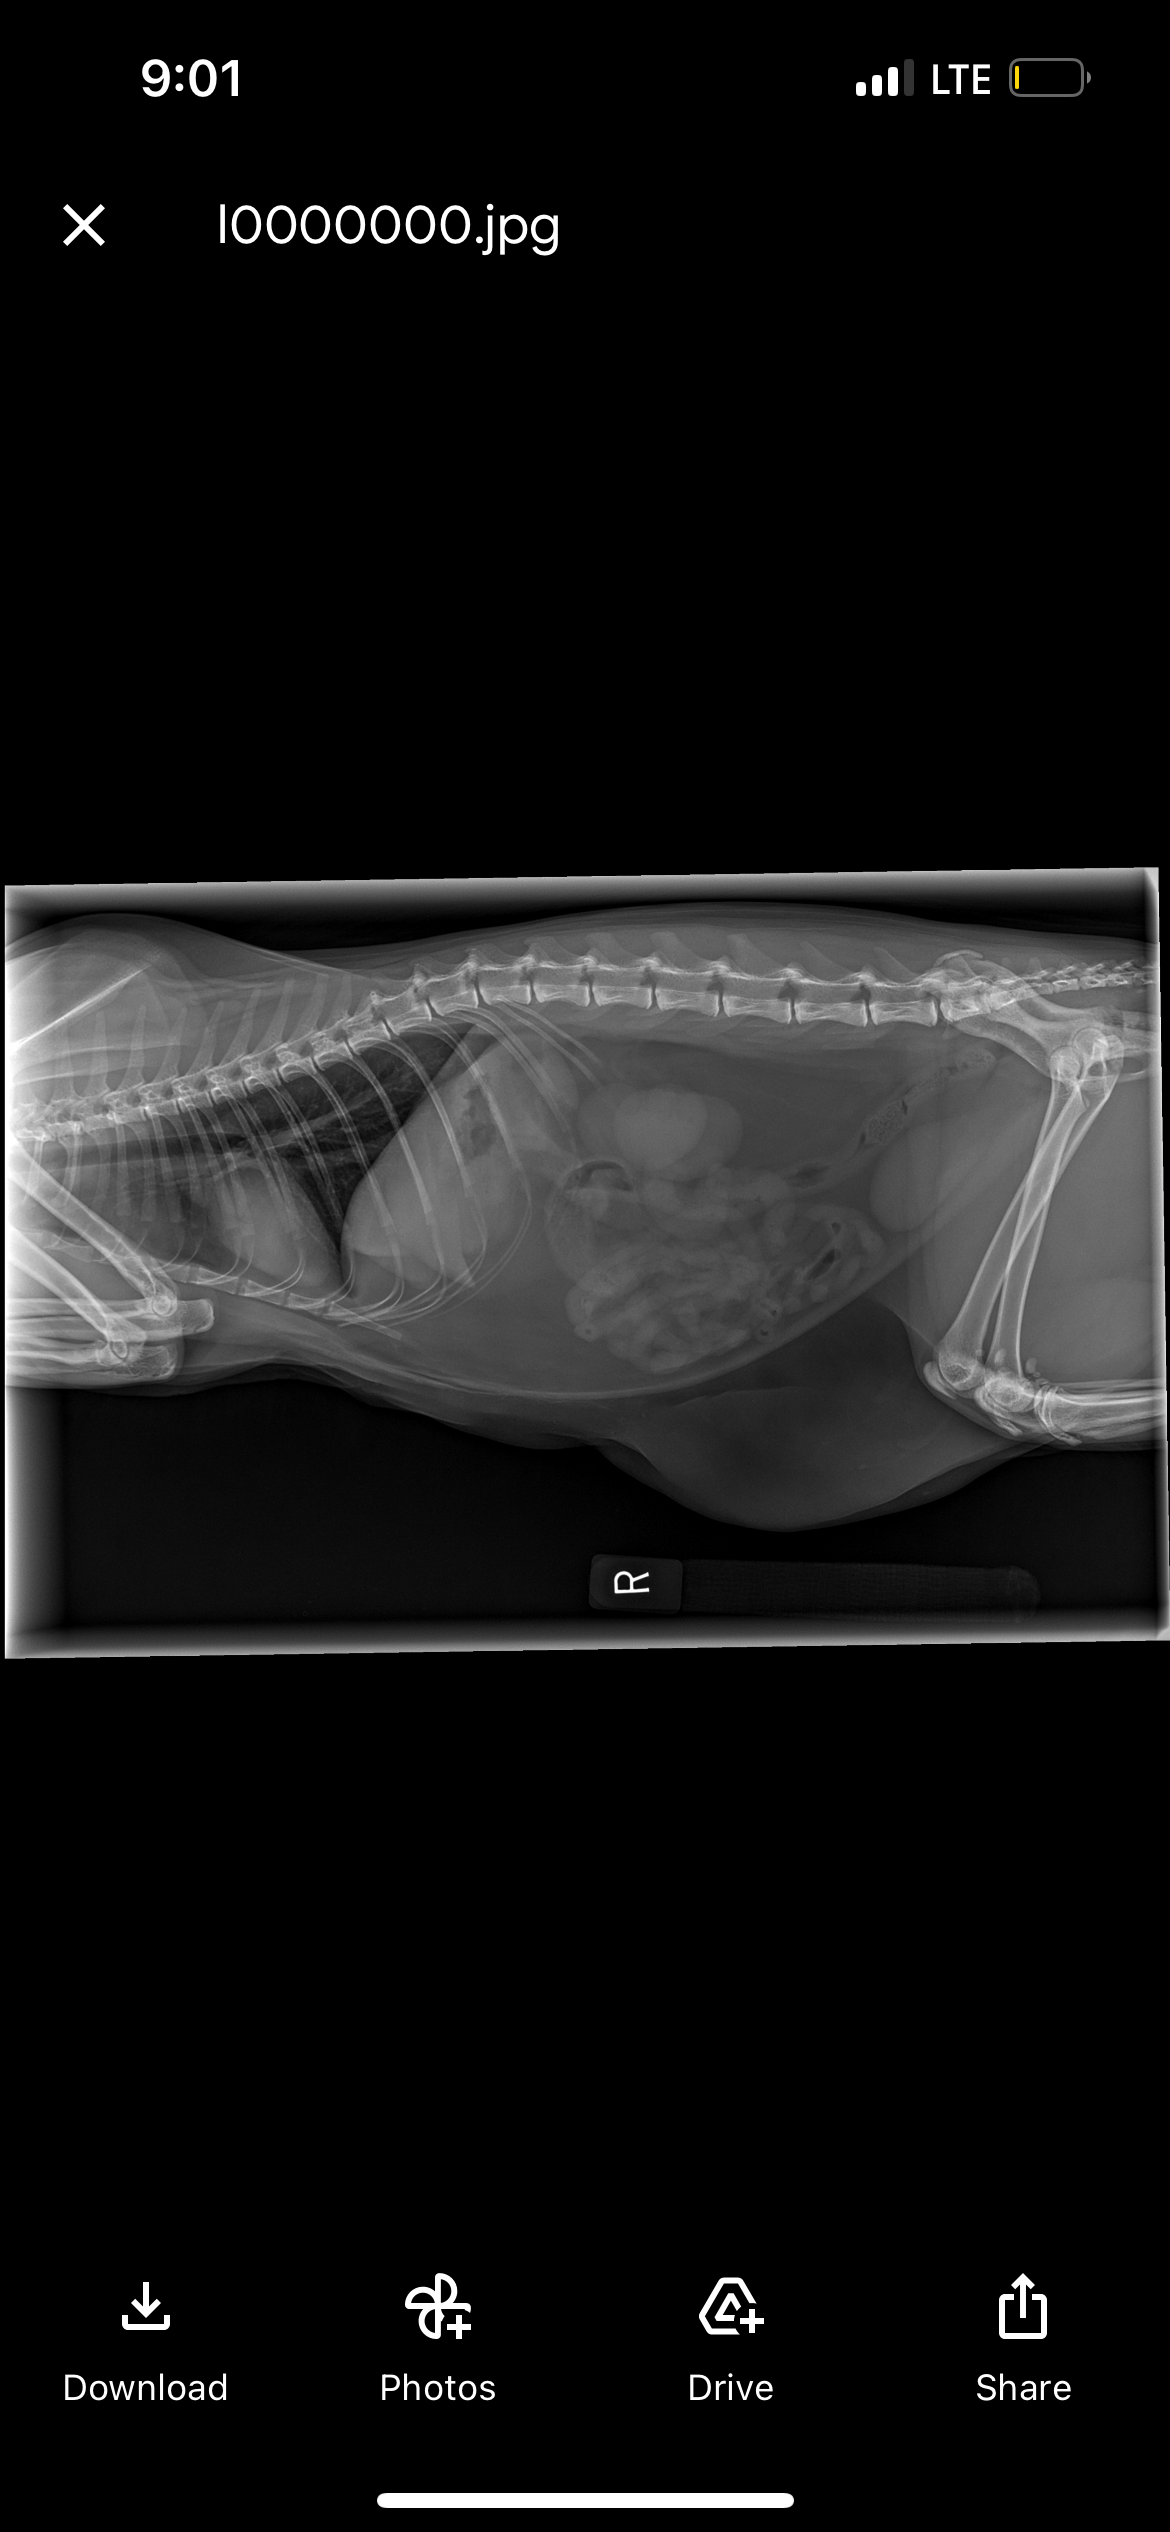

The funds raised will go directly toward Butters’ surgery, which is essential for his health, as well as the expenses for the procedures leading up to it, including X-rays and bloodwork. As college students, covering a vet bill this large is a real and very serious struggle for us. We’re doing everything we can and will continue to, but we need Butters to get medical attention as soon as possible so he has the best chance at a healthy recovery.